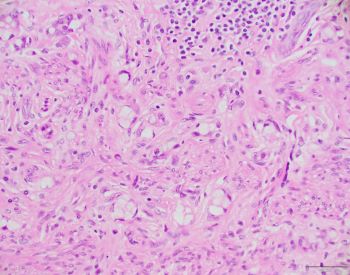

Answer: C. Goblet cell adenocarcinoma.

Tumor cells are present in clusters, appearing as goblet/signet ring cells. The overlying crypt epithelium is not involved. The histologic features are diagnostic of this entity, which is characteristically seen in the appendix with no discrete gross lesion. Immunohistochemical studies are not required. These tumors have to be graded (See 2019 WHO classification) based on the poorly cohesive/solid sheets of tumor cells.